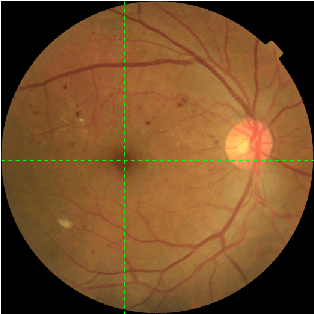

Abstract:Diabetic retinopathy (DR) is a primary cause of blindness in working-age people worldwide. About 3 to 4 million people with diabetes become blind because of DR every year. Diagnosis of DR through color fundus images is a common approach to mitigate such problem. However, DR diagnosis is a difficult and time consuming task, which requires experienced clinicians to identify the presence and significance of many small features on high resolution images. Convolutional Neural Network (CNN) has proved to be a promising approach for automatic biomedical image analysis recently. In this work, we investigate lesion detection on DR fundus images with CNN-based object detection methods. Lesion detection on fundus images faces two unique challenges. The first one is that our dataset is not fully labeled, i.e., only a subset of all lesion instances are marked. Not only will these unlabeled lesion instances not contribute to the training of the model, but also they will be mistakenly counted as false negatives, leading the model move to the opposite direction. The second challenge is that the lesion instances are usually very small, making them difficult to be found by normal object detectors. To address the first challenge, we introduce an iterative training algorithm for the semi-supervised method of pseudo-labeling, in which a considerable number of unlabeled lesion instances can be discovered to boost the performance of the lesion detector. For the small size targets problem, we extend both the input size and the depth of feature pyramid network (FPN) to produce a large CNN feature map, which can preserve the detail of small lesions and thus enhance the effectiveness of the lesion detector. The experimental results show that our proposed methods significantly outperform the baselines.

Abstract:Diabetic retinopathy (DR) is a diabetes complication that affects eyes. DR is a primary cause of blindness in working-age people and it is estimated that 3 to 4 million people with diabetes are blinded by DR every year worldwide. Early diagnosis have been considered an effective way to mitigate such problem. The ultimate goal of our research is to develop novel machine learning techniques to analyze the DR images generated by the fundus camera for automatically DR diagnosis. In this paper, we focus on identifying small lesions on DR fundus images. The results from our analysis, which include the lesion category and their exact locations in the image, can be used to facilitate the determination of DR severity (indicated by DR stages). Different from traditional object detection for natural images, lesion detection for fundus images have unique challenges. Specifically, the size of a lesion instance is usually very small, compared with the original resolution of the fundus images, making them diffcult to be detected. We analyze the lesion-vs-image scale carefully and propose a large-size feature pyramid network (LFPN) to preserve more image details for mini lesion instance detection. Our method includes an effective region proposal strategy to increase the sensitivity. The experimental results show that our proposed method is superior to the original feature pyramid network (FPN) method and Faster RCNN.